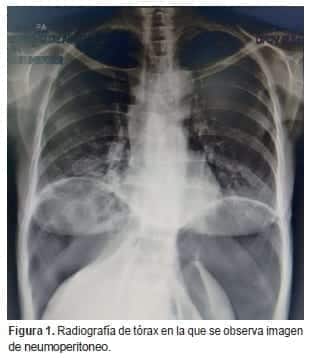

En los exámenes de laboratorio se encontró función renal y hepática normales, no había leucocitosis ni neutrofilia, la albúmina sérica fue de 3,5 g/dl y el VIH fue negativo. En las radiografías de tórax y de abdomen en posición vertical, se observó una gran cámara de neumoperitoneo que desplazaba el hígado y el bazo hacia abajo.

Al no encontrarse signos de irritación peritoneal, se practicó una tomografía toraco-abdominal en la que se observó: derrame pleural bilateral con engrosamiento de las cisuras,

bronquiectasias basales bilaterales, atelectasia parcial de ambos lóbulos inferiores, notoria distensión del esófago con sonda en su interior, hidroneumoperitoneo, abundante líquido libre en la cavidad abdominal y distensión de las asas intestinales (figuras 1-3).